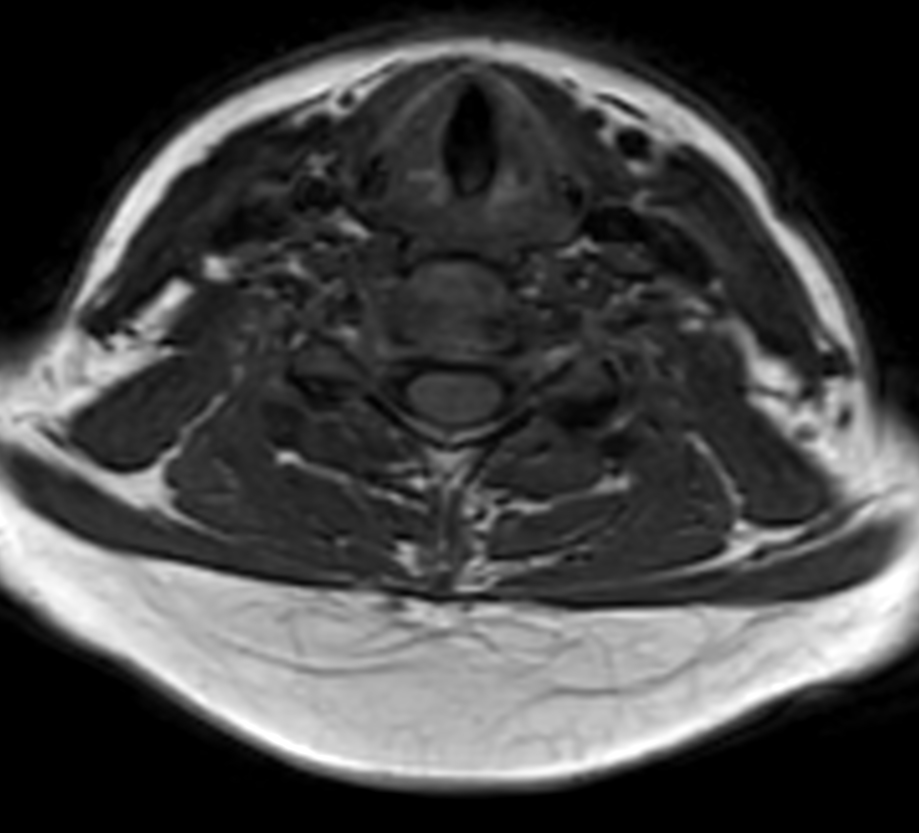

Axial T2w TSE (small FOV)